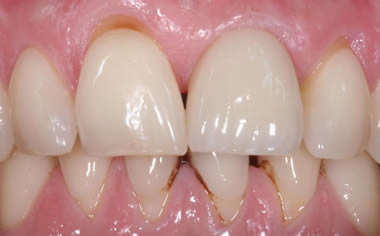

More front teeth replaced by dental implants

Case Three (4 images)